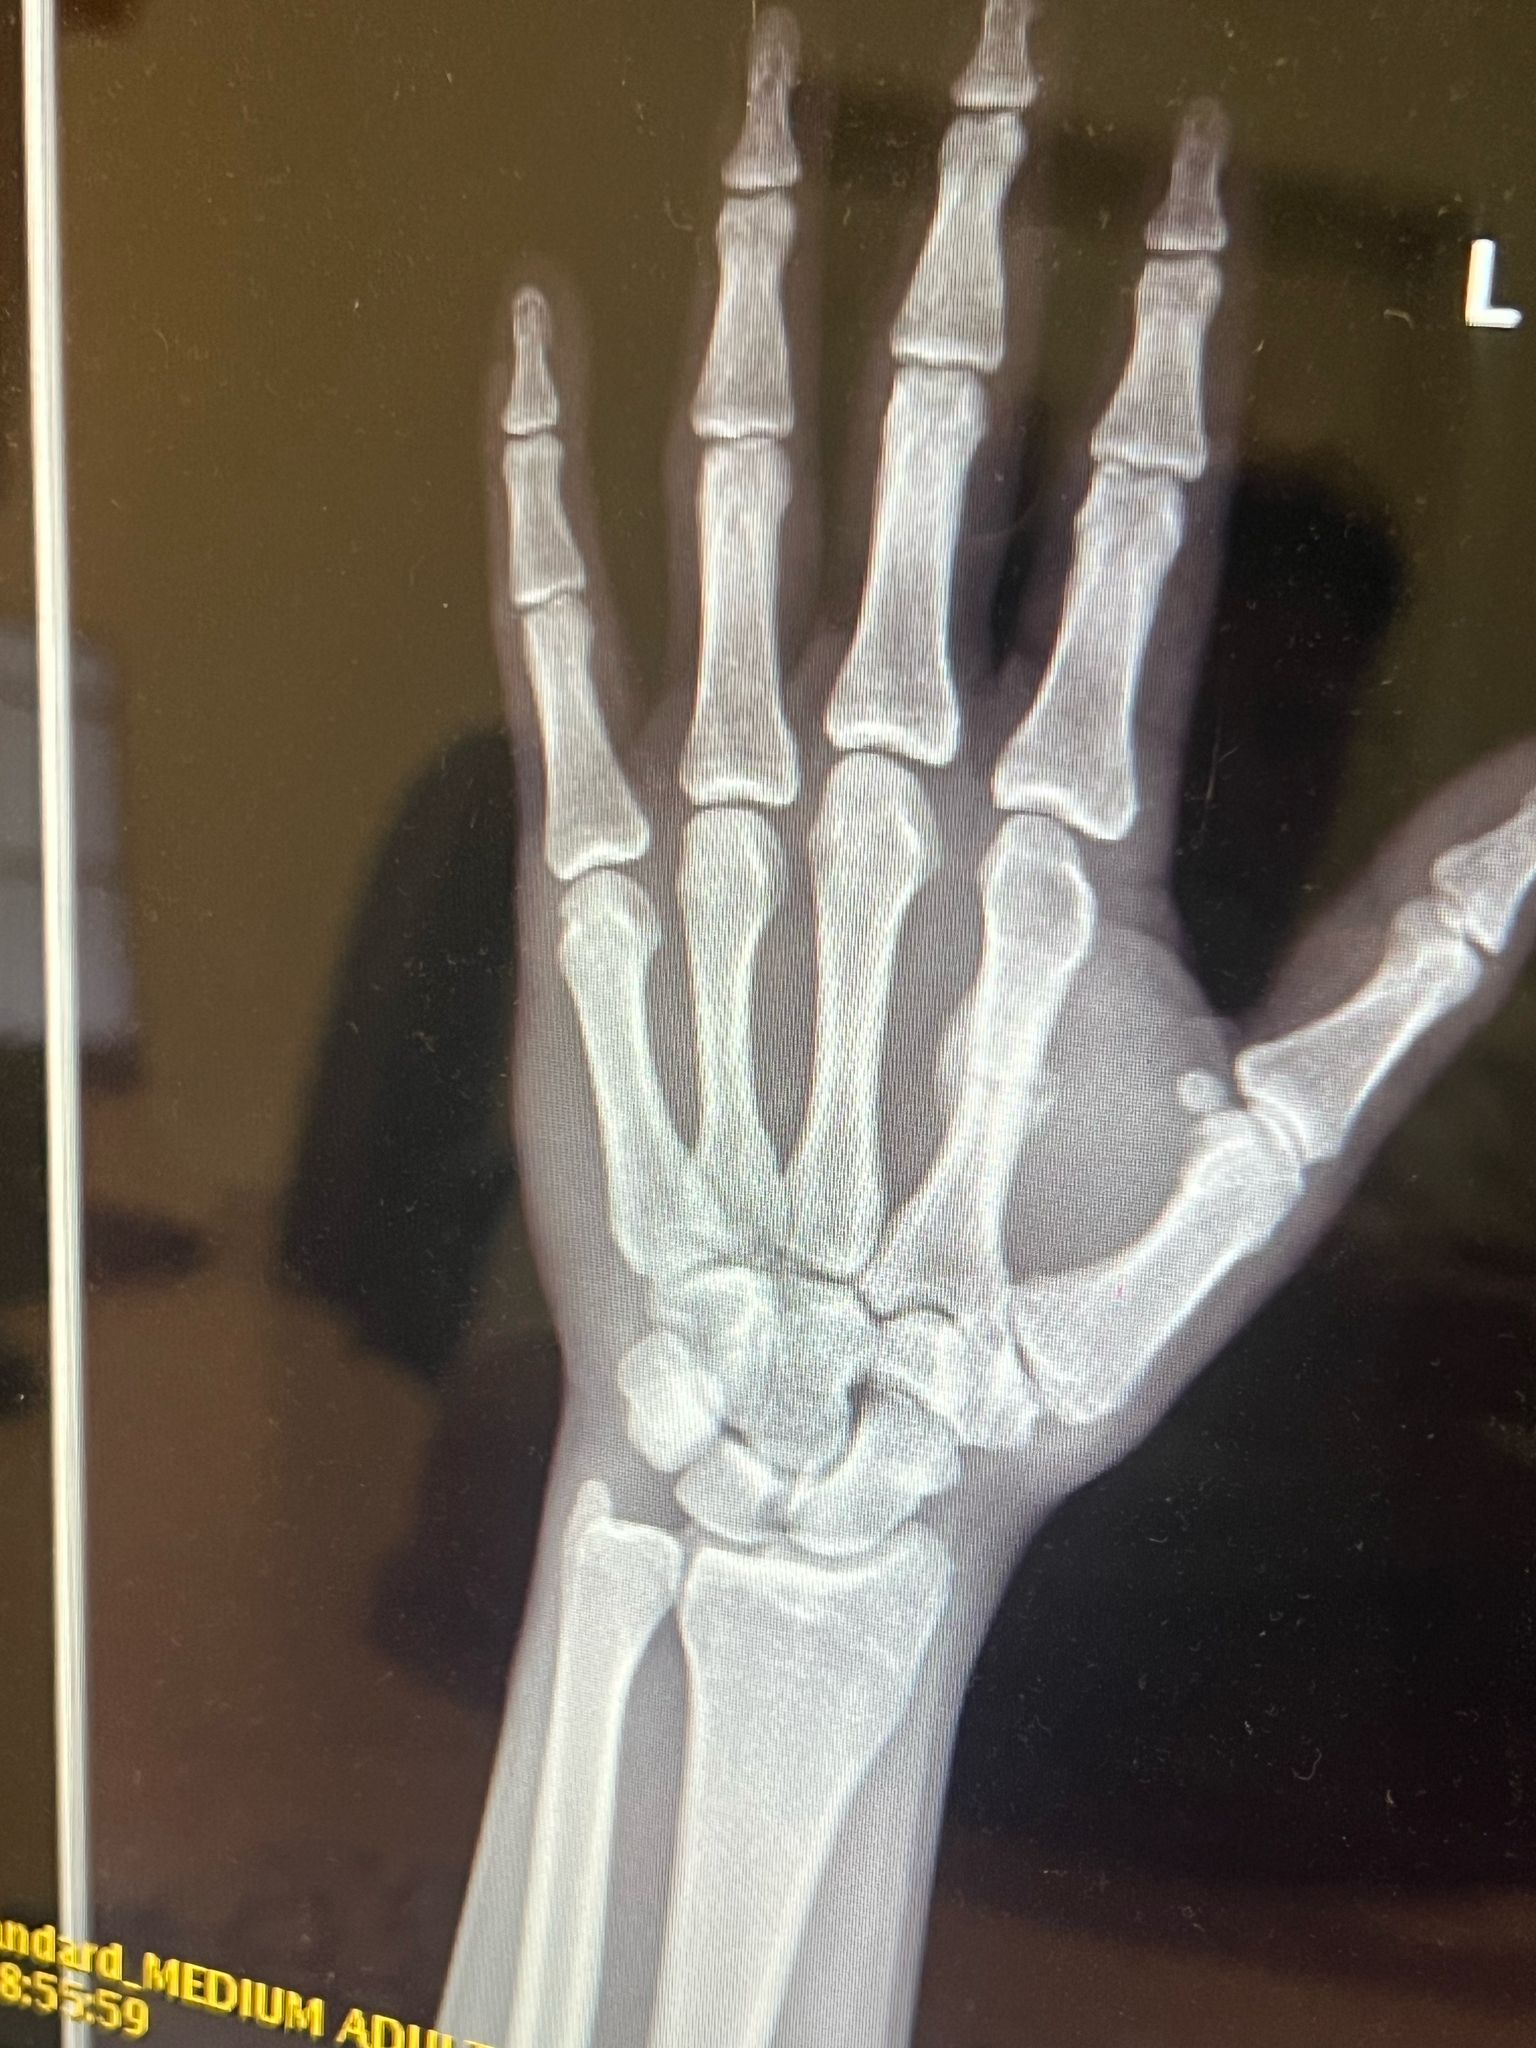

• Zranenie: 4. 6. 2024 – zlomená zaprstná kosť

• Operácia (osteotómia): 27. 10. 2024

• Začiatok liečby: 28. 10. 2024

• Koniec rehabilitácie: 22. 12. 2024

Osteotómia je chirurgický zákrok, pri ktorom sa kosť prerezáva a presne nastaví tak, aby mohla správne zrast. Po takejto operácii predstavuje hlavnú výzvu najmä kvalita zhojeného kostného tkaniva, opuch, bolesť a obmedzenie pohyblivosti. Práve terapia LIMFA tu zohrala kľúčovú úlohu.